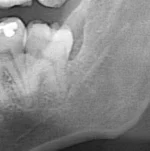

Idę dziś po pracy do chirurga stomatologa usunąć ósemkę. Pierwsze rwanie stałego zęba w życiu. Dajcie kilka plusów na odwagę ( ͡° ͜ʖ ͡°) W sumie to bym jej nie usuwał, bo sama w sobie nie przeszkadza, ale zrobił się nad jej częścią kaptur dziąsłowy, co powoduje częste stany zapalne. Pocieszam się, patrząc na zdjęcie, że robota raczej nie będzie skomplikowana, jak w przypadkach gdzie ząb jest zupełnie